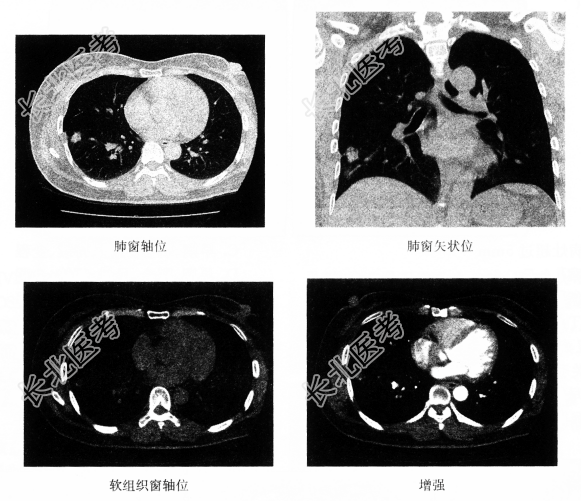

- [材料题] 患者女,50岁,一周前无明显诱因下出现咳嗽,伴咳少许白色黏痰,无胸闷气促、无发热盗汗,听诊无异常发现。胸部CT如下图所示。

- 单项选择题1.该病变的部位是

A、右肺中叶

B、右肺下叶

C、脊柱

D、右侧胸壁

E、肝

F、右上肺

- 单项选择题2.结合病史,该患者最可能的诊断是

A、肺脓肿

B、肺癌

C、炎性假瘤

D、肺结核

E、转移瘤

F、大叶性肺炎